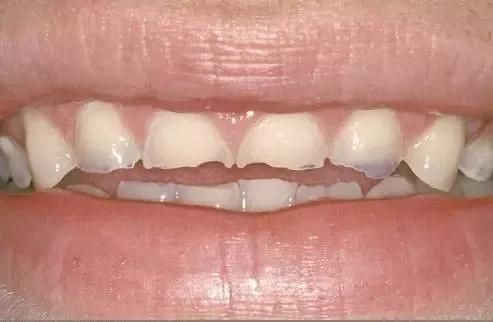

夜磨牙也是导致牙釉质损害的“隐藏敌人”。有夜磨牙的人,长年累月不正常的紧咬牙齿和磨耗牙齿,使得釉质被磨掉或折裂。

这张图上能看到上下前牙都被磨低了

磨牙症在夜间表现得最为严重,而此时你是无法控制自己的,一般来说放松自己、减少压力可以减轻症状。

如果发现自己有这样的问题,可以咨询牙医,通过佩戴一种特殊的牙齿保护套来减少对牙釉质的损害。